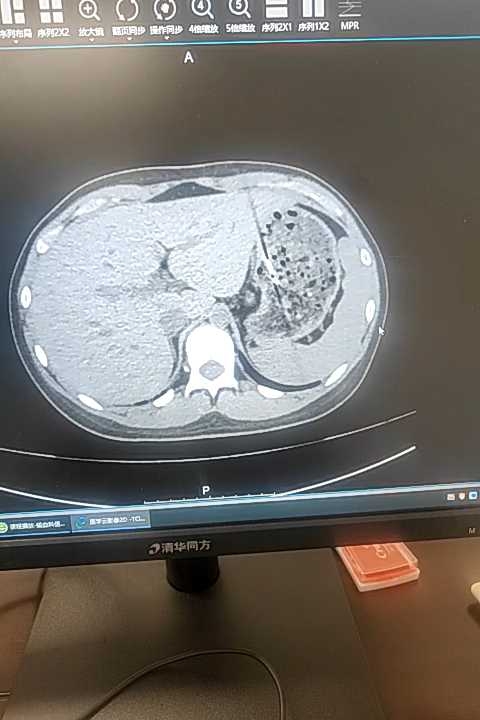

患者女,13岁,因食吞刀片5小时入院。既往史无特殊。查体无特殊。入院完善CT检查示